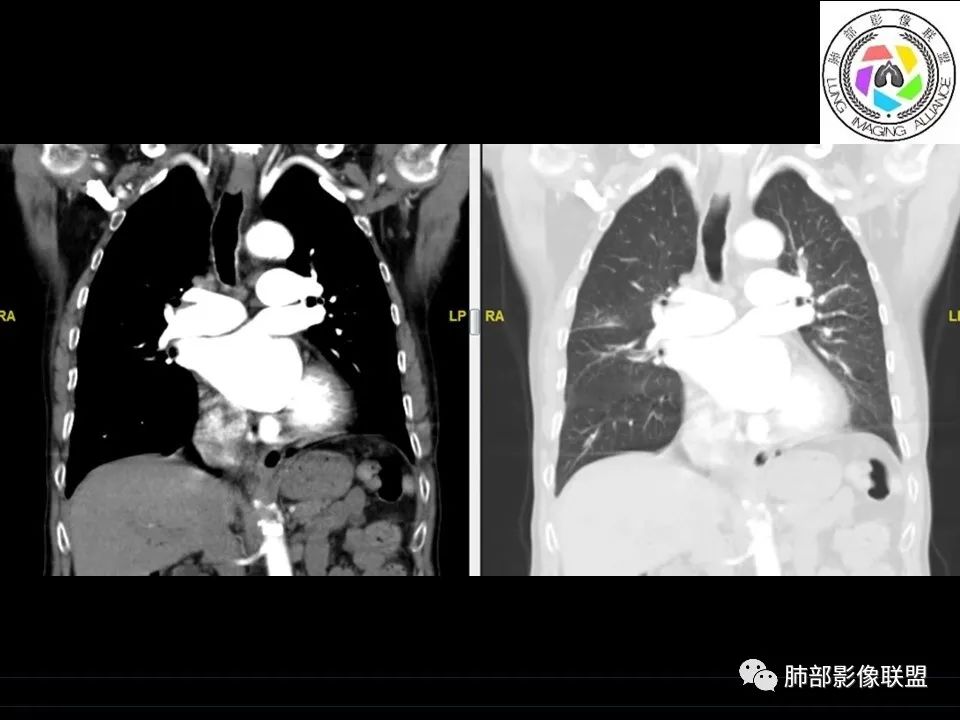

1、老年男性,右侧后胸壁软组织肿块延伸范围较广(至后纵隔主动脉旁),平扫密度均匀稍高,增强扫描均匀强化,其间走行肋间动脉包埋、漂浮(夹心三明治),部分包绕肋骨,肋骨骨质未见明显吸收破坏!

2、胸膜掀起或尾征,胸壁肋间肌及脂肪间隙浸润,肋间动脉供血。

3、纵隔淋巴结多发肿大,部分有融合。 医学百科网 | YxBaike.Com

4、双侧未见典型胸膜斑,提示石棉非长期接触。胸膜病变不广泛。淋巴结改变与胸膜病灶不相称。

5、良性胸膜间皮瘤局限、规则高密度。恶性间皮瘤胸膜呈波浪状,常伴胸水。

6、老年患者转移瘤多见。双侧多发,易伴胸水。胸壁侵犯肋骨破坏为主。常有原发肿瘤。